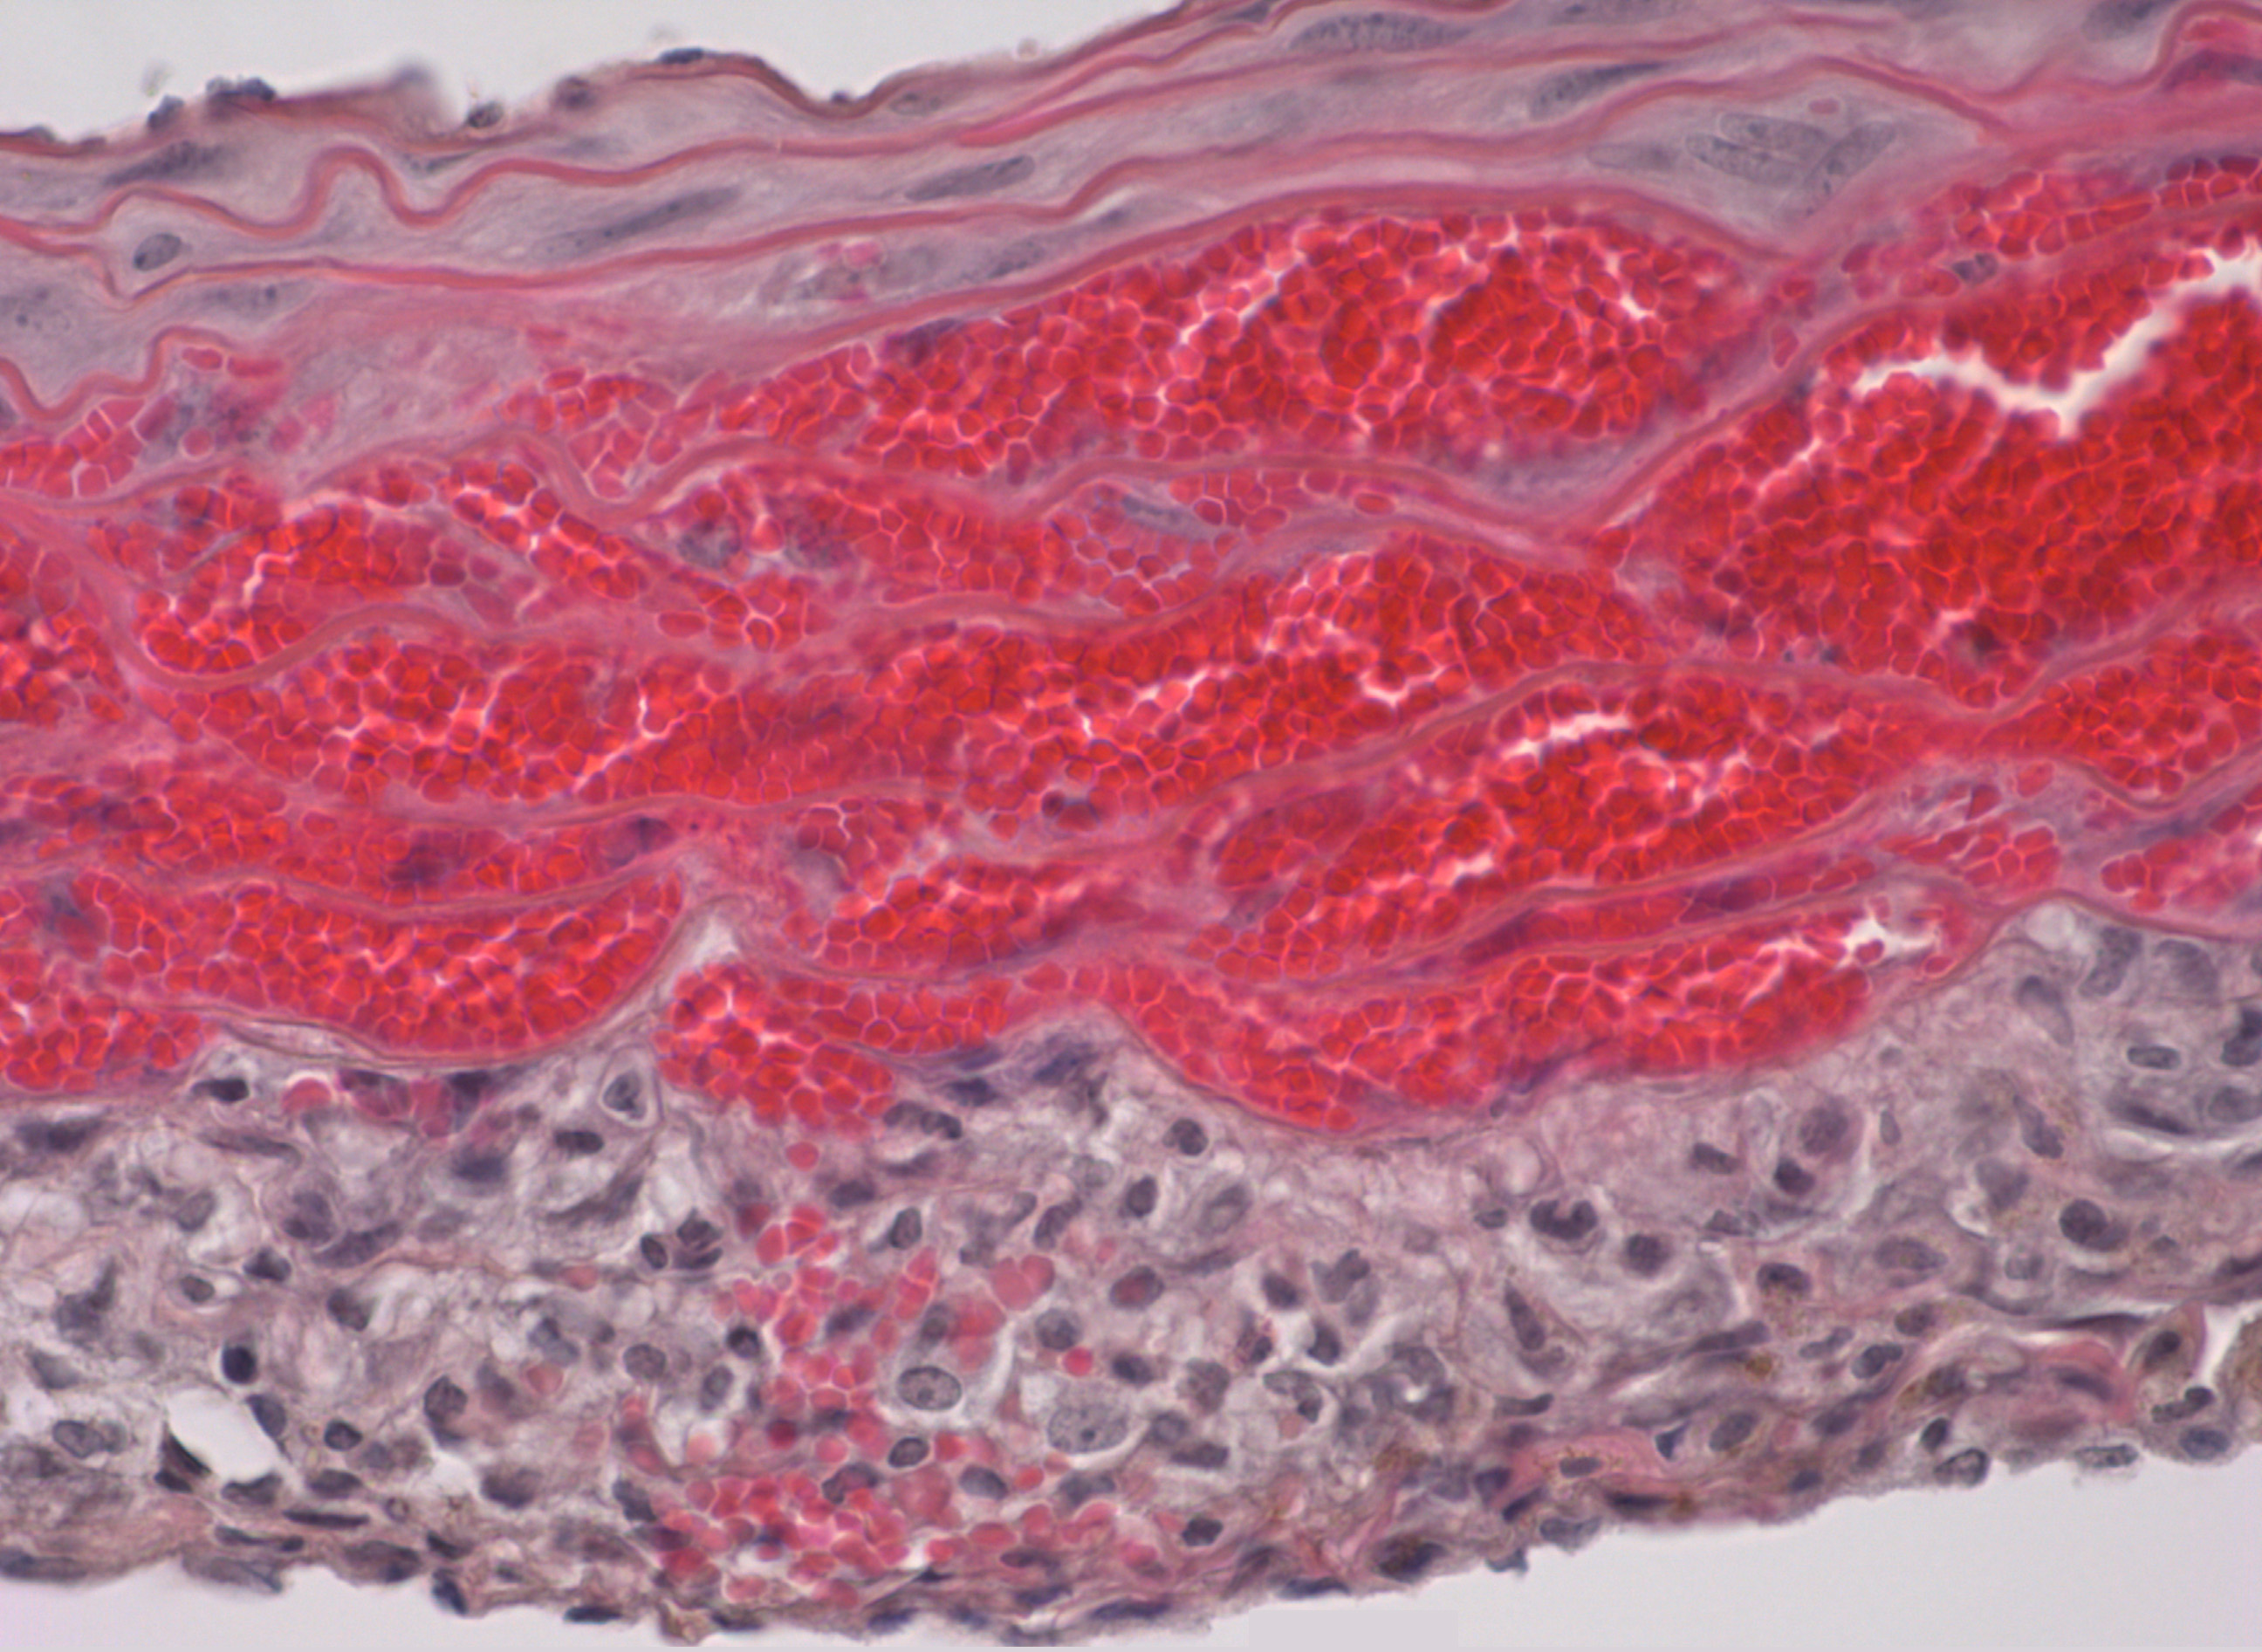

Imagen microscópica de hematoma intramural en el modelo preclínico de la enfermedad. Se muestra la acumulación de la sangre invadiendo la capa media de la aorta

El hematoma intramural consiste en una acumulación de sangre dentro de la pared de la aorta sin disección (desgarro) de su capa íntima (la capa más interna, en contacto con el torrente circulatorio). En los pacientes afectos, el hematoma intramural puede, en su fase aguda, reabsorberse espontáneamente o evolucionar con rapidez a disección aórtica en su fase aguda, explican los investigadores. Por otro lado, la evolución más común a largo plazo de esta enfermedad conduce hacia el desarrollo de un aneurisma, es decir, una dilatación o ensanchamiento anómalo de una porción de la aorta, que también puede provocar su rotura y, por lo tanto, la muerte del paciente.